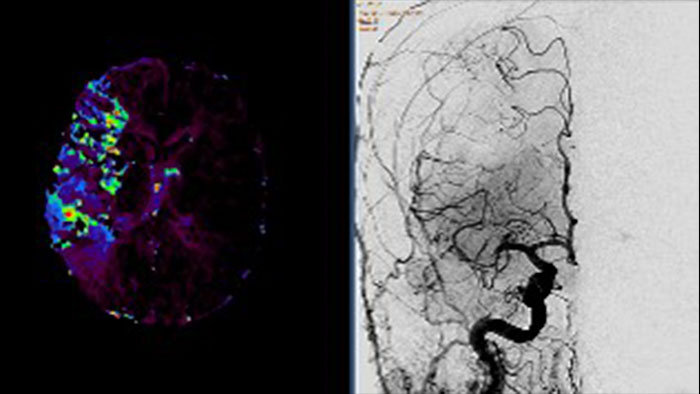

Support in assessing lesions by reviewing blood supply characteristics

Designed to evaluate time intensity curves of a T1 signal enhancement series. The application produces measurements including relative enhancement, maximum enhancement, time to peak (TTP), and wash-in/wash-out rates.

Lesion characterization by reviewing vascular leakage

Designed to visualize T1 weighted DCE 3D datasets and assist in analyzing the tissue response.